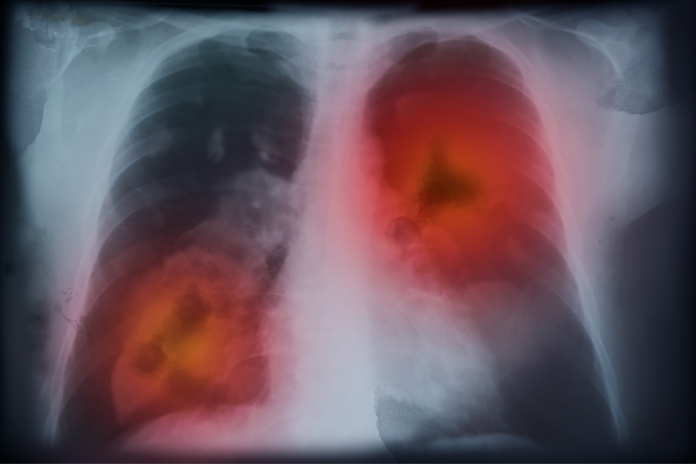

El Grupo Español de Cáncer de Pulmón (GECP) alertó que la mortalidad por cáncer de pulmón sigue en aumento entre las mujeres impulsada por un incremento en su incidencia del 5,4% en la población femenina en España, según los últimos datos facilitados por el Instituto Nacional de Estadística (INE) en su informe ‘Defunciones según la causa de muerte. Definitivos 2022 y provisionales del primer semestre de 2023’.

Según este informe, las neoplasias de pulmón ya suponen la cuarta causa de muerte global en España y la primera por cáncer. Unos datos que preocuparon a los especialistas del GECP.

Tal y como explicó el experto, “nos enfrentamos a un problema sanitario de gran calado. Hay que volver a poner el foco en la lucha contra el cáncer, sobre todo en el de pulmón, que en la actualidad aglutina el 20% de todas las muertes. El total de fallecidos por esta causa en 2022 equivalieron a la suma de muertes de cáncer de mama, próstata y de colon en España”.

Así, cerca de 22.700 españoles perdieron la vida como consecuencia de un cáncer de pulmón en 2022, una mortalidad que permaneció estable en hombres (0%), pero que se incrementó un 5,4% en mujeres, respecto a 2021. La mortalidad absoluta en mujeres aumentó un 134% desde 2003.